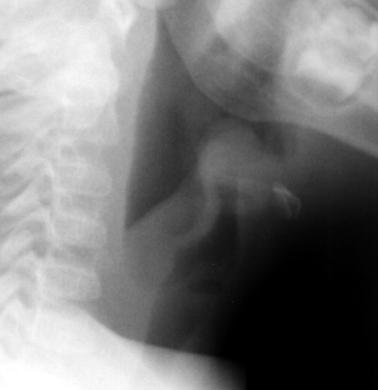

ZNAKI ZLOMA NOSNIH KOSTI: Oteklina, odmik nosne piramide vstran, očalasta podplutba ob nosnem korenu, krepitacija, krvavitev iz nosnih votlin, Če prelom sega v sitko pri palpaciji tipljemo podkožni emfizem.